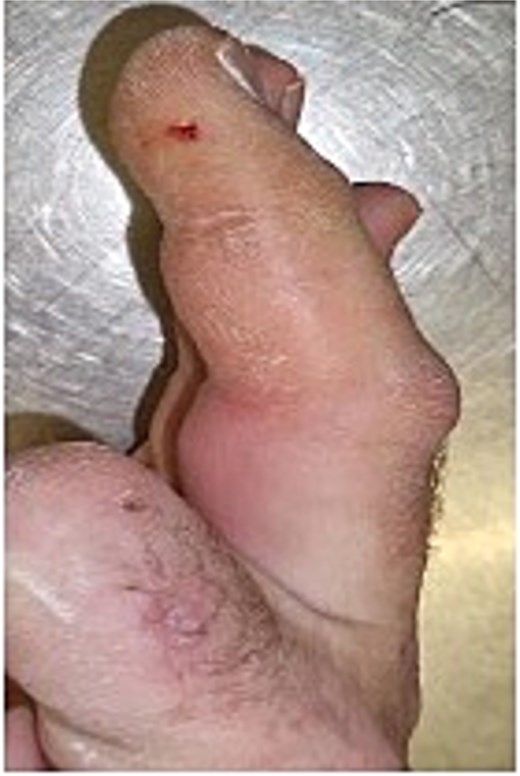

Initial presentation (Fig. 4) with accompanying X-ray (Fig. 5) and intra op image during first debridement (Fig. 6).

X-ray image of patient two showing injected material into volar surface of his digit.